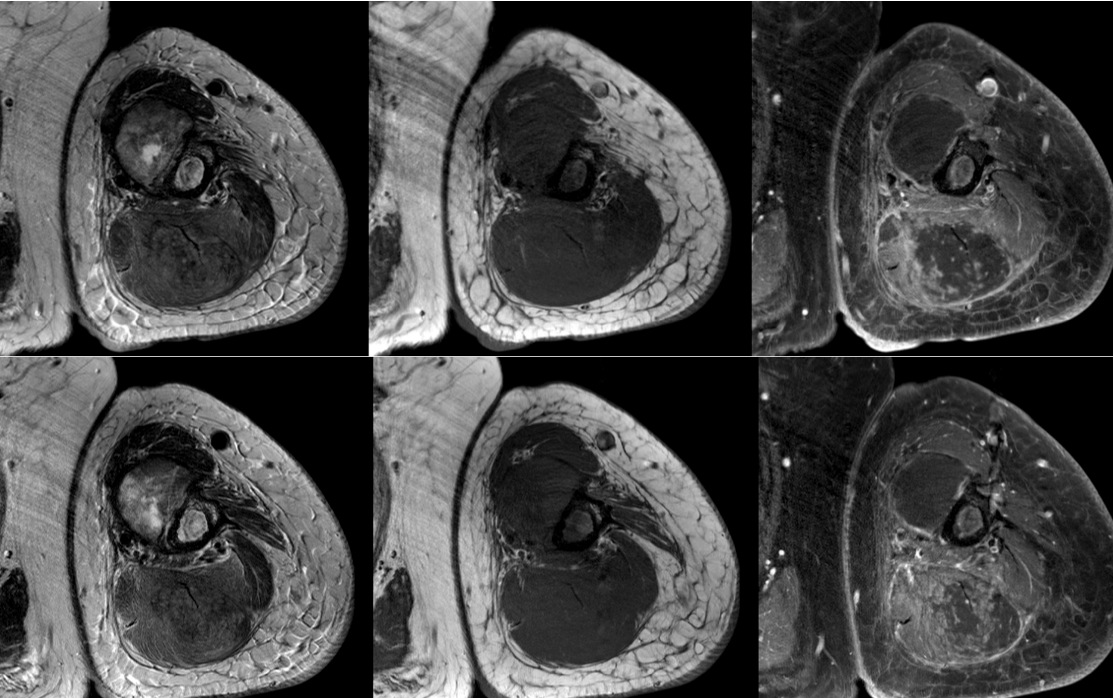

Figure 2 for case Radiation induced myonecrosis

Figure 2